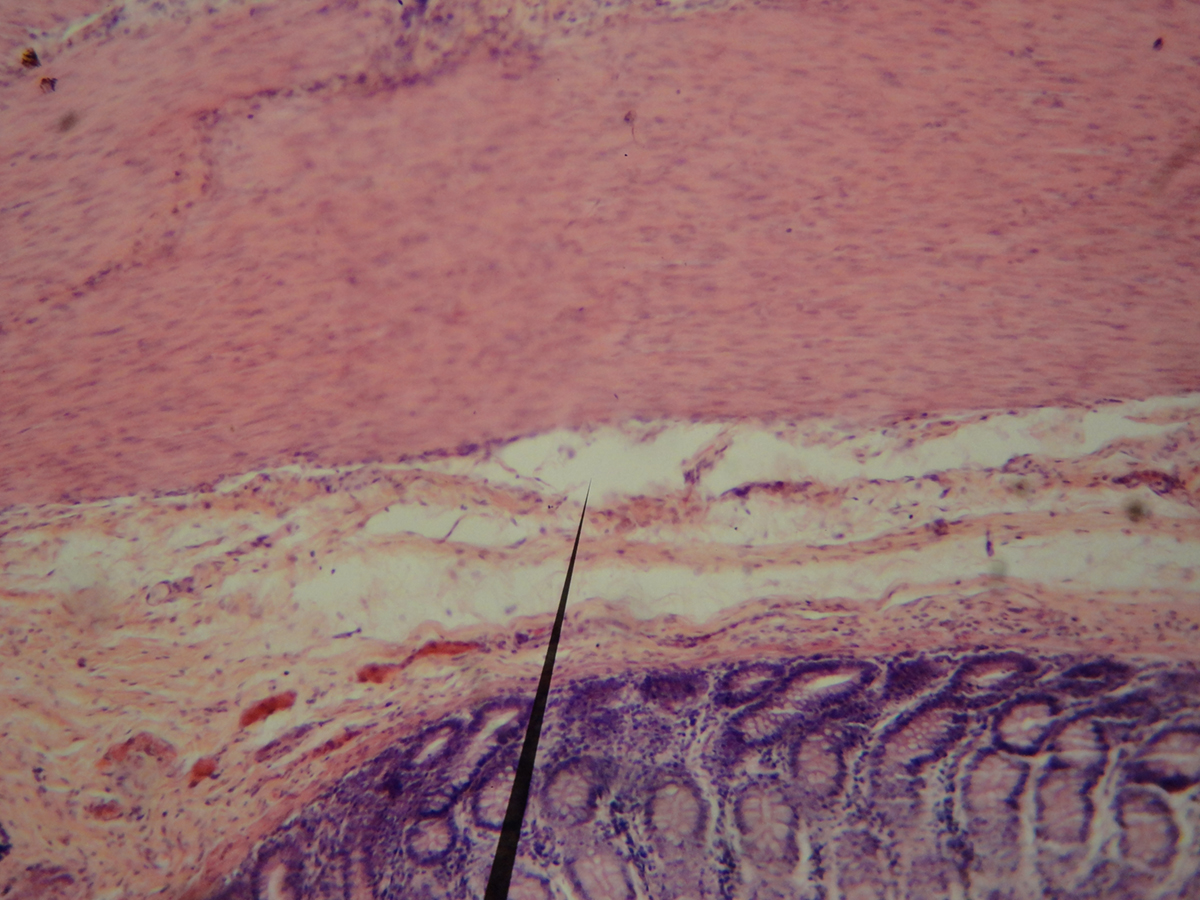

Small intestine blockage is medically known as ileus. The condition may develop due to many illnesses of the gastrointestinal tract. For example, a hernia is one of the common causes of small intestine blockage. In such cases, the obstruction develops after the hernia traps the loop of the small intestine.

Furthermore, similar effects may occur if one is suffering from an intestinal tumor. The tumor grows inside the affected part of the small intestine and once it becomes too large it simply interrupts the passage of the stool by completely blocking the inside of the intestine.

People who have undergone abdominal surgery are at risk of adhesions. Such fibrous tissue bands between different structures in the abdomen may be responsible for the small intestine blockage.

Apart from the previously mentioned that accounts for approximately 90% of all cases of small intestine blockage the remnant 10% include blockage caused by twisting of the intestine (medically known as volvulus), inflammation, and scarring associated with Crohn's disease, intussusception (invagination of one portion of the small intestine into another section of the intestine), chemical or electrolyte disturbances, intra-abdominal infection, kidney/lung disease and intake of certain medications or drugs.